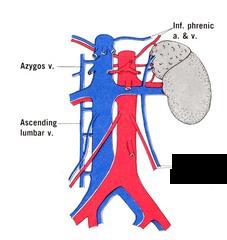

Aortic Arch

Ascending/descending aorta

Thoracic aorta

Abdominal Aorta